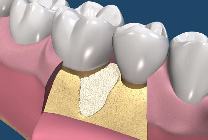

牙周再生手術是一種要求較高的牙周手術,其成功取決於多種條件的滿足,這些條件是:嚴格的適應證選擇;牙齦的炎症被有效控制;骨內袋中的肉芽組織應當儘可能被清除;生物膜在齦溝“領口”處應與牙根面盡量密合,以保證無齦上皮長入;生物膜與牙根之間應保持充分的空間,即足夠的膜根間隙;齦瓣應將生物膜完全覆蓋;術前術後有效的菌斑控制。(圖07-11)

圖9